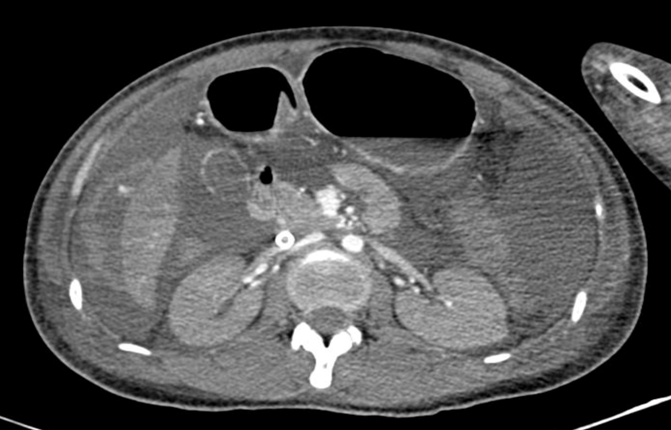

Hình 1. Dịch ổ bụng lượng nhiều, nghi ngờ chảy máu ổ bụng trên phim chụp cắt lớp vi tính

Bên cạnh việc truyền máu tích cực, việc tìm nguyên nhân chảy máu là một vấn đề cấp bách được đặt ra, nếu không bao nhiêu lượng máu hiếm quý như vàng lại tiếp tục chảy ra. Hình ảnh trên siêu âm cũng như chụp cắt lớp cho thấy dịch ổ bụng lượng nhiều, nghi ngờ có máu trong ổ bụng. Người bệnh sau đó được nhanh chóng chuyển lên phòng mổ kèm theo hệ thống ECMO để can thiệp nội soi ổ bụng cấp cứu dưới sự thực hiện của BS. CKII Phan Lương Huy khoa Ngoại tổng quát. Nhờ sự can thiệp kịp thời và chính xác, ổ chảy máu được xác định nằm ở phân thùy VI của gan nhanh chóng được can thiệp đốt cầm máu, ca phẫu thuật bước đầu đã thành công.